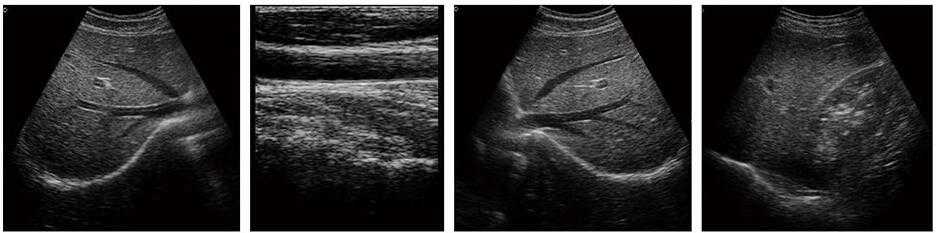

DW-370黑白B超機

3、適用于常規腹部、子宮附件、淺表組織等臨床檢查

1、掃描方式:凸陣、線陣、微凸

2、顯示模式:B、2B、4B、B/M.M